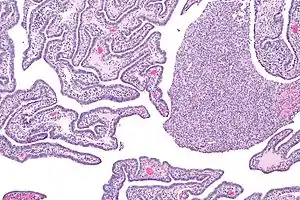

| ریزنگار بافت درگیر سالپنژیت حاد و مزمن. | |